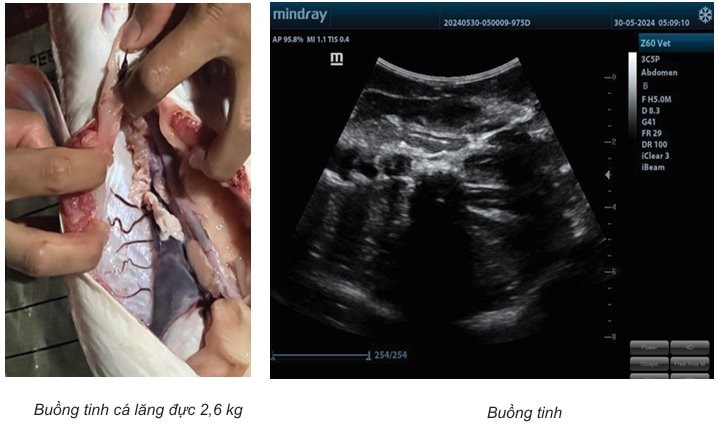

Nghiên cứu đã xác định được loại đầu dò và tần số siêu âm một số cơ quan nội tạng cá lăng và cá tra. Đầu dò Micro Convex tần số 5,0 MHz và Convex tần số 3,5-5,0 MHz là những đầu dò nên dùng để siêu âm cơ quan nội tạng của cá lăng và cá tra ở vị trí mặt bụng và mặt bên của cá. Đối với cá lăng, có thể dùng thêm đầu dò Linear tần số 5,0-10,0 MHz khi khảo sát các cơ quan ở vị trí mặt bụng cá.

Phương pháp siêu âm đối chiếu giải phẫu cá/tiêu bản tuyến sinh dục cá đã cho thấy được sự tương quan hình ảnh, vị trí của các cơ quan. Từ kết quả nghiên cứu đã xây dựng được kỹ thuật siêu âm tuyến sinh dục của cá lăng và cá tra. Nhóm nghiên cứu đã tiến hành đo đạc và đưa ra khuyến cáo khi kiểm tra kích thước buồng trứng đối với các nhóm cá ở các kích cỡ khác nhau.